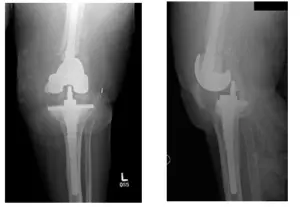

X-Rays show preoperative changes of left TKA reconstruction

Patient received an aspiration of the left knee to check for infection. Results showed that the patient had an infected knee tumor prosthesis. Patient was advised to receive an articulating antibiotic prosthesis with high dose articulating antibiotic spacers to treat the infection.

Antibiotic spacers will be left in for approximately 6-8 weeks and will then be removed and replaced with a new prosthesis. Patient had decided to proceed with the surgery.

Pre-Surgical X-Rays show left TKA dislocation with dorsal translation of the tibia and widening of the tibiofemoral joint

X-Rays show left knee intraoperative changes including long stem femoral and tibial prosthesis